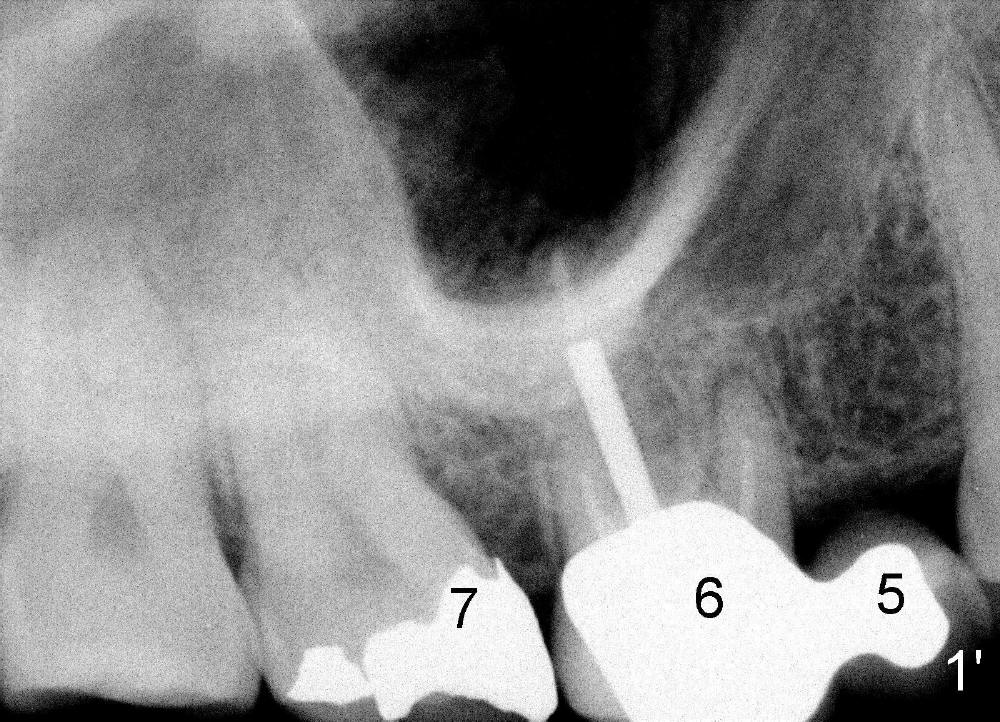

五十一岁Junita牙齿不好,右上有一个悬臂桥(图一’:5.6),她要找一位医生能解决她所有的牙科问题:右上7牙髓炎(图一’),右下,左下6植牙(图’四)。她最大问题是害怕牙科治疗,根管治疗中不太配合:牙胶尖插入后拍摄X光片,位置不对,没有显示根尖(图二’),最后根管充填效果尚可(图三’),疼痛没有了,病人的心被我们收买了,接着我们准备分期给右下,左下6植牙,但是她坚决反对,要求一次完成两个植牙,因为她非常怕痛,对钻耳环洞都害怕极了,做了一个耳环(图’四:箭头),再没有勇气回去做第二个。好了,明天做二个植牙,到时向大家汇报。这位胆小病人上战场时胆怯了,迟到一会儿,说她不愿意左右各做一个植牙,影响吃饭。由于右下近远中间隙比左下大些,我们先做右下植牙,回学术讨论园地